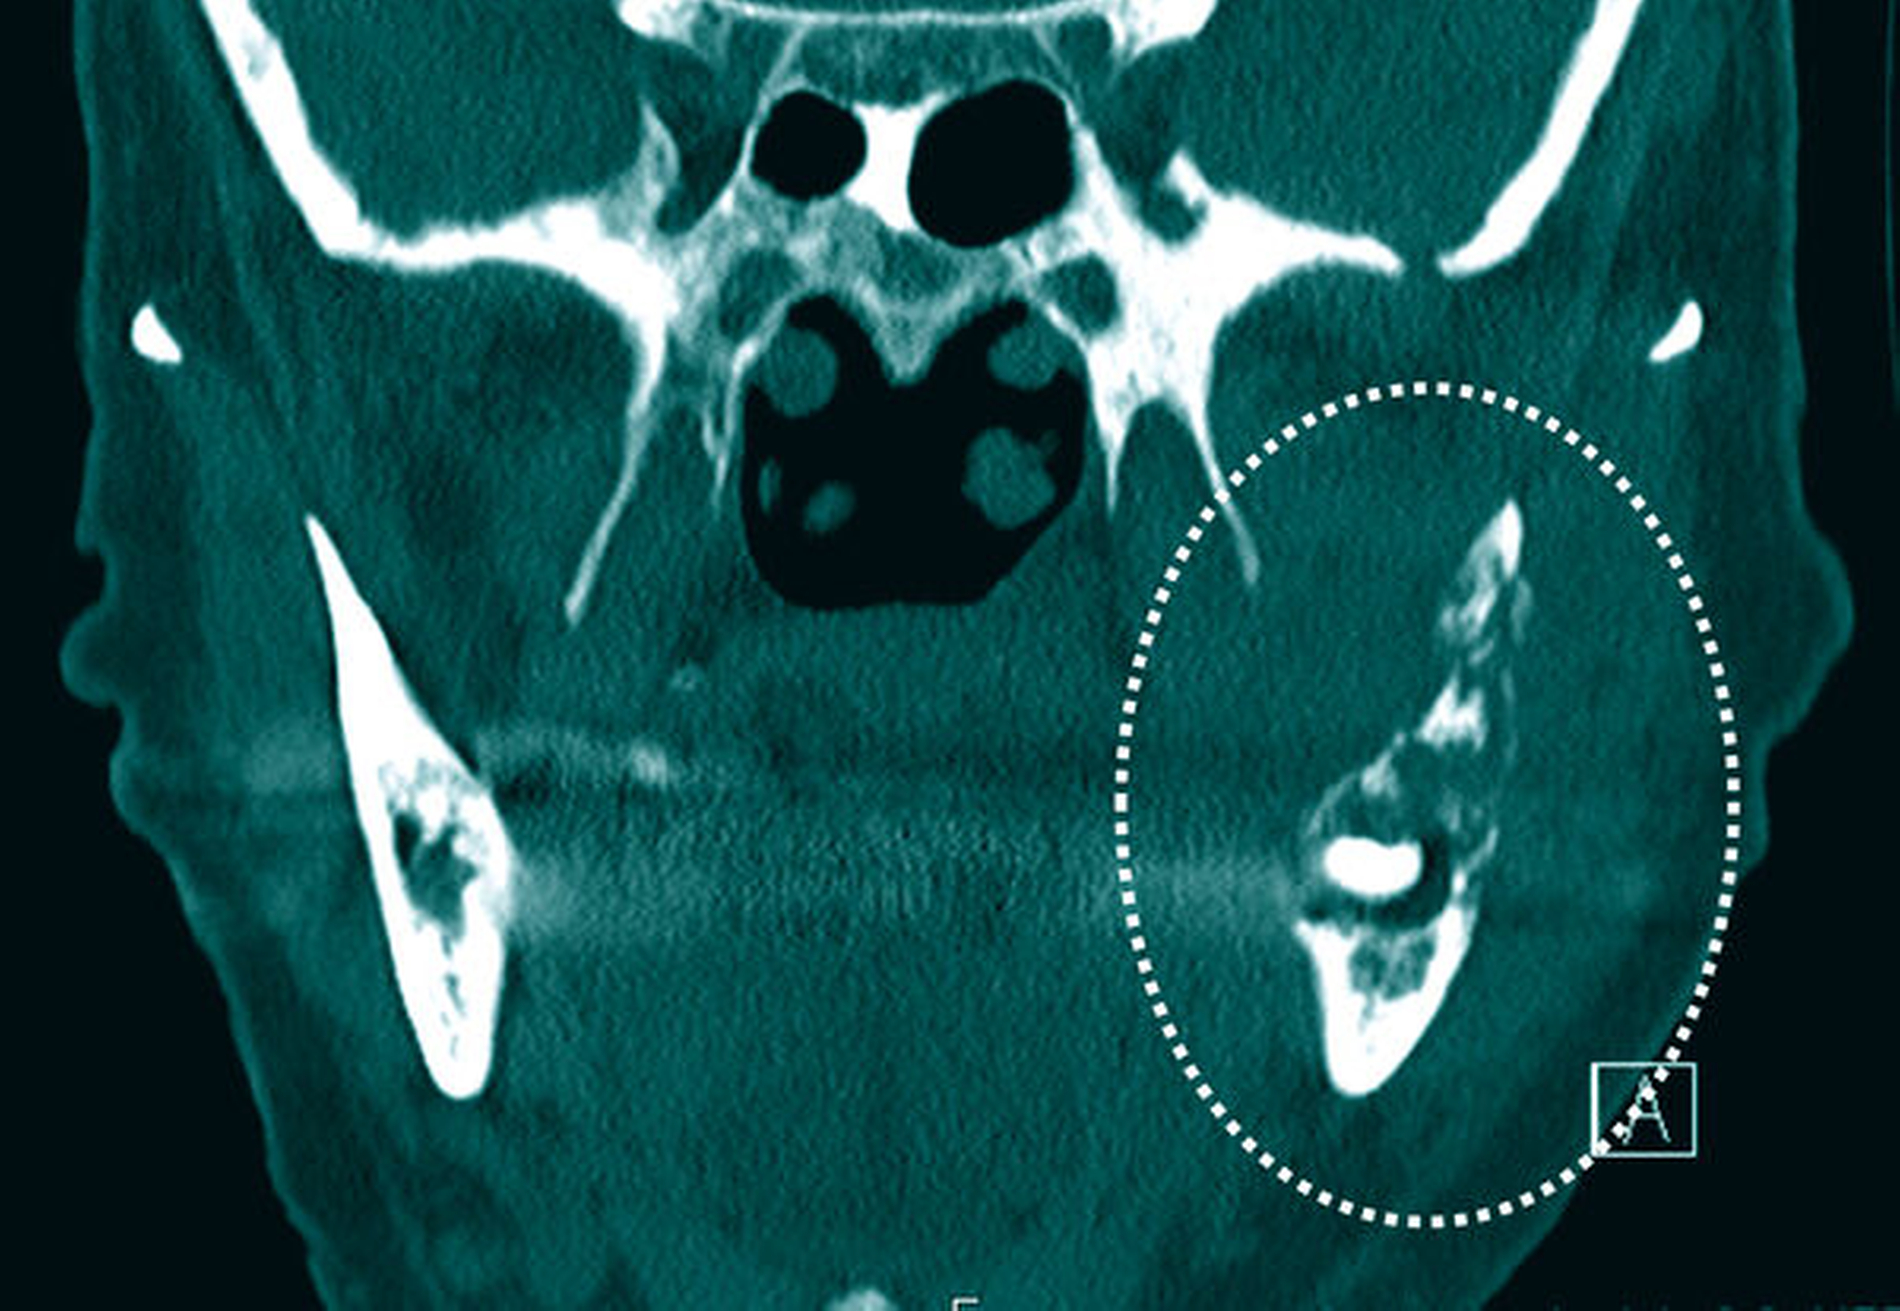

Klinisch wurde zunächst die Verdachtsdiagnose einer ausgedehnten Osteo-radionekrose beziehungsweise einer ossären Spätmetastase des vorbekannten Mammakarzinoms gestellt. Die CT-Bildgebung bestätigte eine ausgedehnte Osteolyse von regio 37 bis hin zur Schädelbasis mit allseitigem Befall der knöchernen Kortikalis (Abbildung 2). Zusätzlich zeigte sich eine massive, den linken aufsteigenden Unterkiefer- ast vollständig umschließende Raumforderung (Abbildung 3).